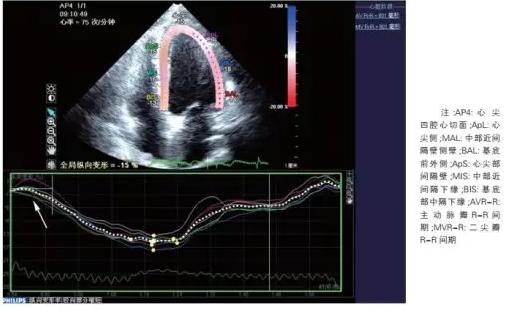

令人振奋的是一些新进的研究发现,超声也有可能直接诊断冠心病。来自大连医学院附属大连市中心医院的研究发现,应用二维斑点追踪技术表明,中度以上的冠脉狭窄患者心肌的收缩早期时间明显延长,延迟时间为 60.0 ms可作为诊断值(敏感度为 85.5%,特异度为74.1%,AUC=0.91),该研究发表在《中国循环杂志》上。

图片来源:中国循环杂志

研究者们认为,冠心病时由于部分心肌长期缺血,导致心肌纤维化和心肌肥大,发生心肌重构。当心脏收缩时,左心室压力增高,缺血部分心肌没有足够的主动收缩力来对抗左心室强大的压力,左心室整体纵向收缩功能减低,出现收缩早期的延迟现象。